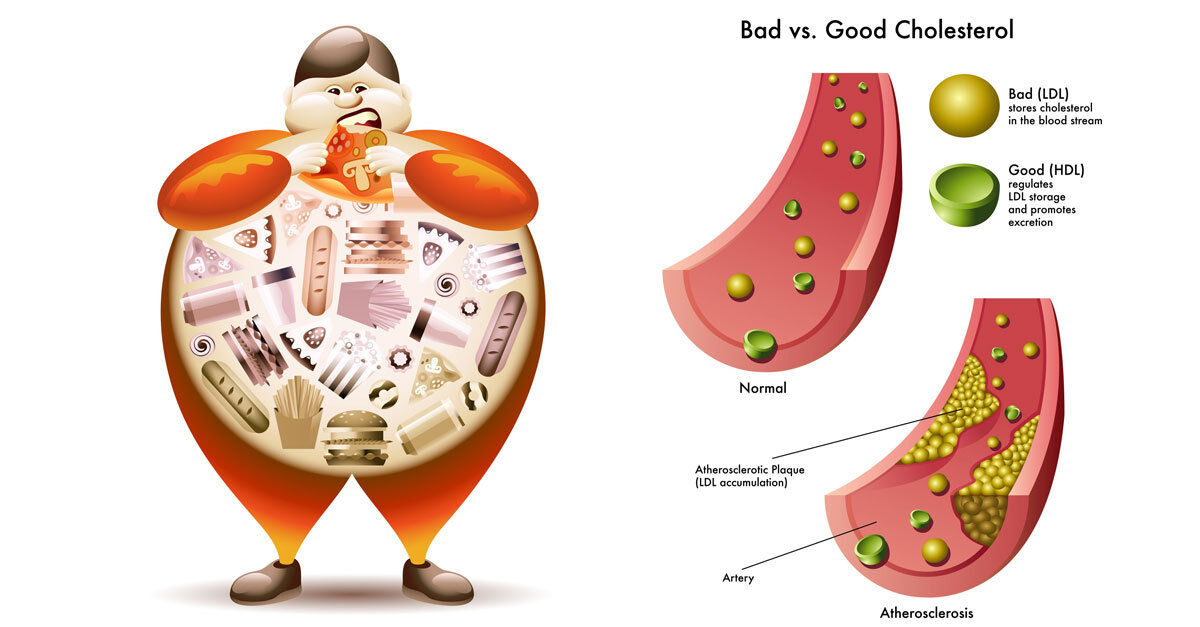

Холестерин в организме: влияние и функции (схемы и диаграммы)